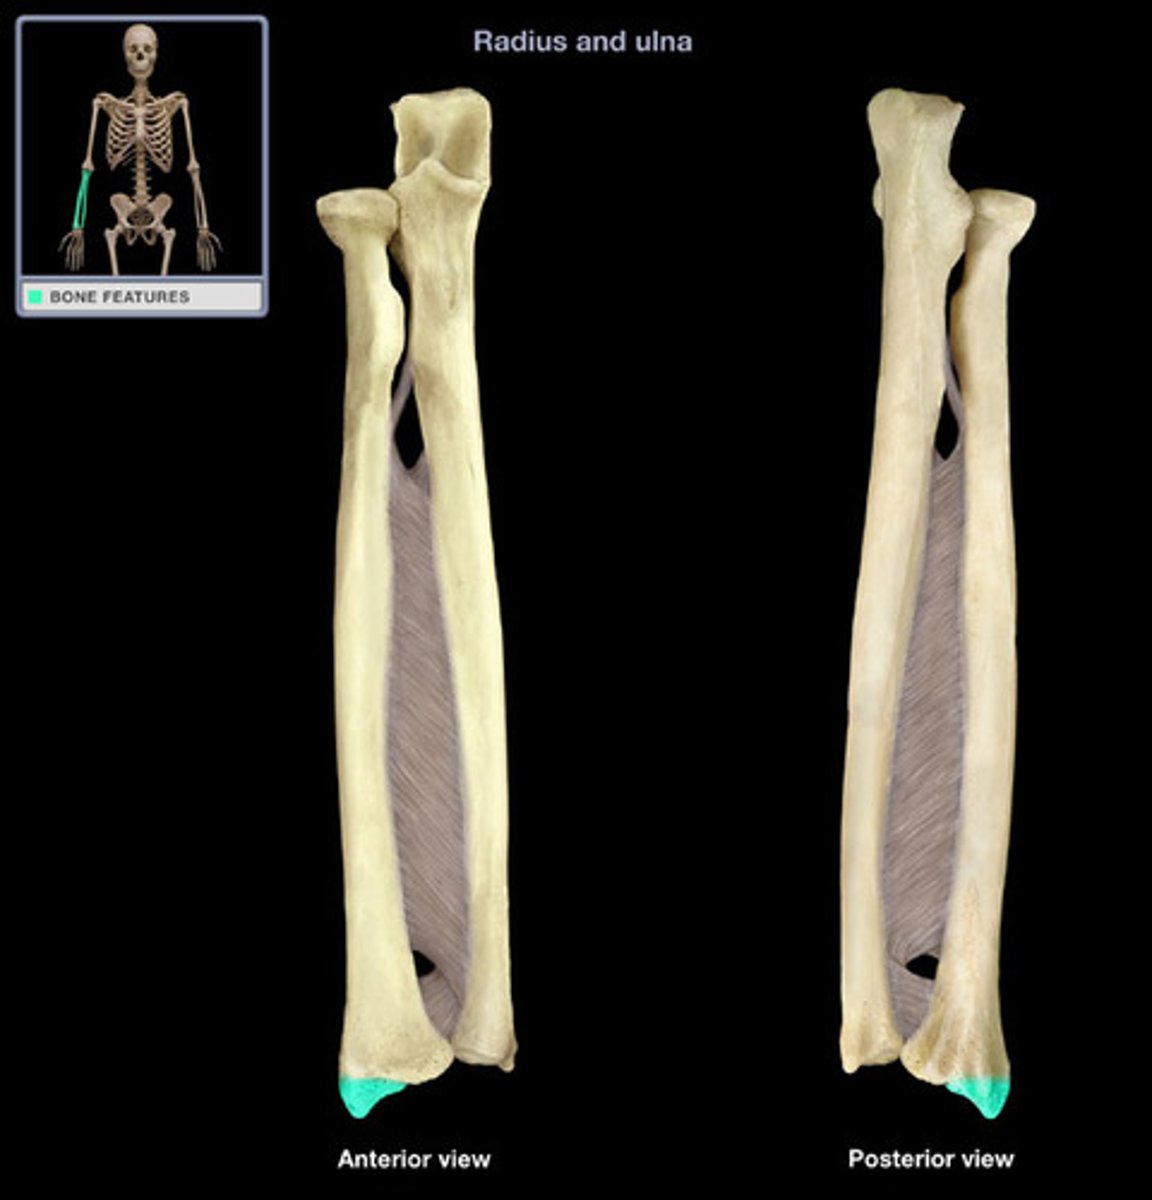

Radius

lateral bone of the forearm, in line with the thumb

Distal radius

insertion of pronator quadratus

Radial head

articulates with capitulum of humerus, proximal

radial styloid process

the pointed structure at the distal end of the radius

Ulna

Inner and larger bone of the forearm, attached to the wrist and located on the side of the little finger.

Ulnar styloid process

distal pointed projection; located medial to the head of the ulna

Ulnar head

distal end of ulna